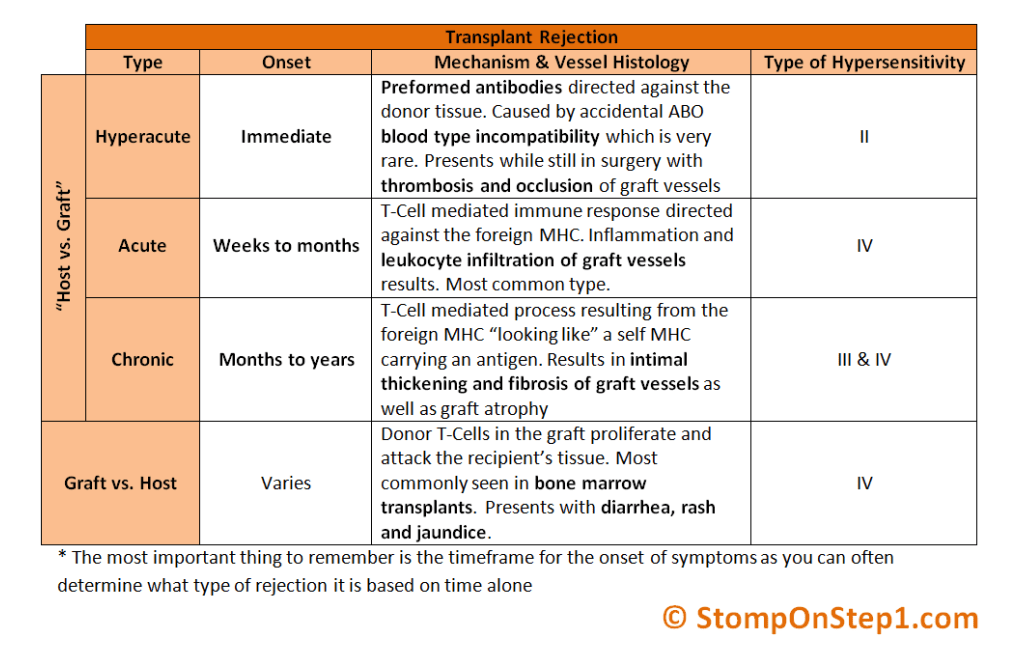

- Rejection time lines

- GVHD TX

- Tx:

- glucocorticoids; high dose

- Calcineurin inhibitors

- Empiric abx

- Tx: